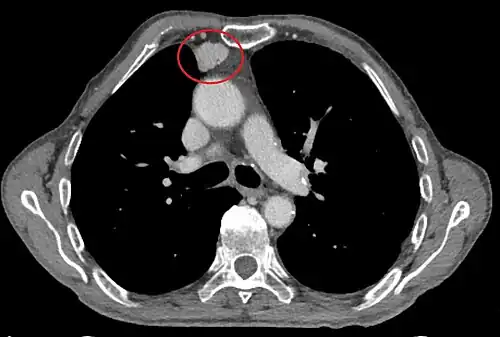

Scanner injecté, en fenêtre médiastinale, montrant un carcinome thymique envahissant les structures médiastinales :

1 : tumeur hétérogène, aux contours irréguliers, présentant des plages hémorragiques ;

2 : veine cave supérieure ;

3 : tronc artériel brachiocéphalique ;

4 : artères sous-clavière gauche et carotide commune gauche ;

5 : crosse de l'aorte ;

6 : sternum.- Scanner en fenêtre parenchymateuse, montrant un carcinome thymique envahissant les poumons (avec des lésions d'emphysème) au contact des deux poumons (1 : poumon droit ; 2 : poumon gauche) ;

flèches noires : zones suspectes d'envahissement.